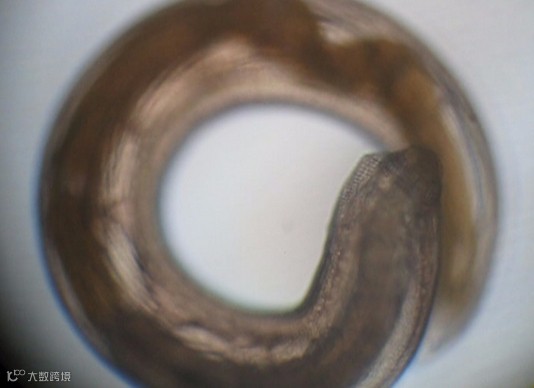

实验君把它放在解剖镜下观察。我勒个苍天!一大片蠕动的虫子!透明的表皮,黄色和白色的身体,有的展开身子像蚯蚓一样游动,有的盘起来像螺蛳一样!可以想象这些家伙在我们的胃里会是什么样!

颚口线虫

医生说,从黄鳝沉渣里挑出来的叫做颚口线虫,用肉眼看非常小,最长的可能也就几毫米,实验人员在我们买的10斤黄鳝中,找到了250条颚口线虫!而这些只是颚口线虫的幼虫,它们在黄鳝体内还会长大!

下面这只“未成熟”成虫看起来就明显大了几倍,褐色的身体,头还在转动。

看到了吗?即使经过咀嚼、胃液消化4小时后,这种虫子仍然能在你体内存活!